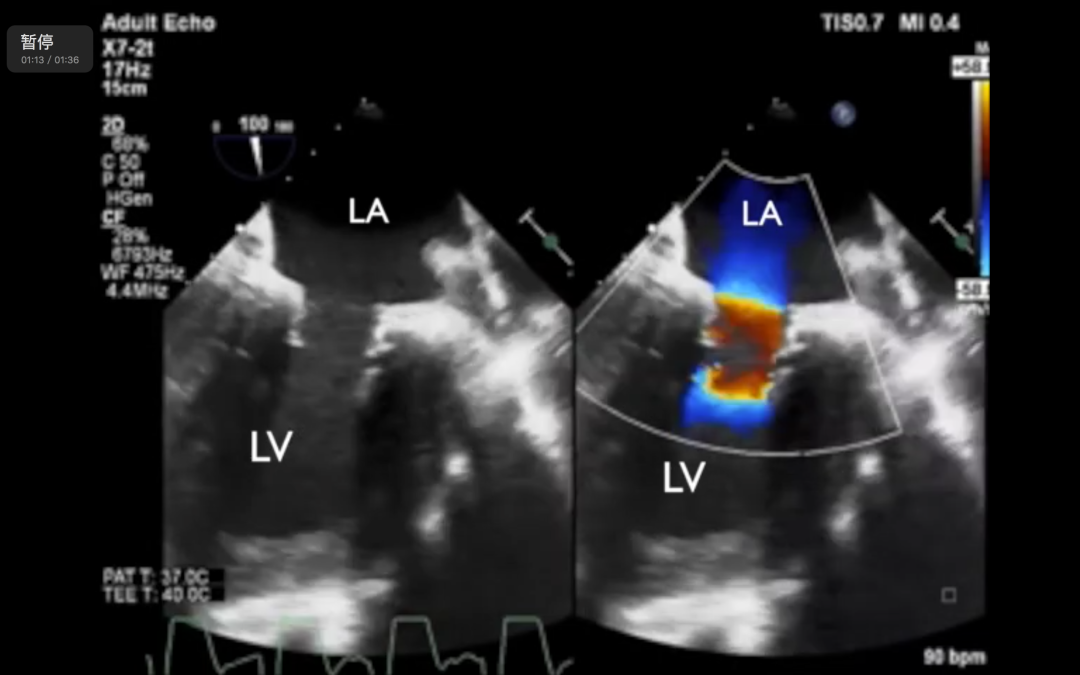

2019年6月,潘湘斌教授团队又在全超声引导下完成了MitraFix®的首次FIM研究。患者术后恢复情况良好,已完成1、3个月和6个月术后随访。

MitraFix®的输送系统中内置了2个标示旋转方向和进入深度的超声标记,可以在超声影像中清晰地显示出与瓣环的相互位置关系。整个释放过程无需精确捕捉瓣叶或瓣下结构,因而对操作和定位精度的宽容度较大,这也是该产品只需依靠超声影像引导即可完成植入过程的主要原因。

潘湘斌教授指出,MitraFix®是能够以同一个瓣膜同时适用于经心尖和经股静脉输送系统的二尖瓣介入置换产品。其输送系统拥有独一无二的全超声引导设计,使得产品仅需要超声影像引导就可以完成植入定位,在超声下可以实时监测瓣膜状态,操作简便,学习曲线短。